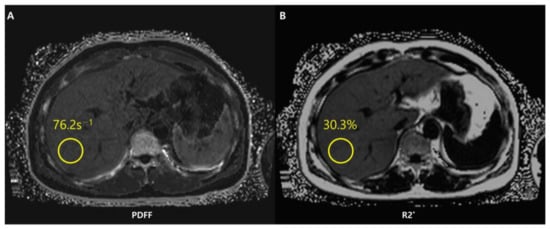

Figure 7.

Chemical shift-encoded (CSE)-MRI allows an estimate of both fat in the liver and iron deposition simultaneously. Fat-corrected R2* mapping (A) is a standard byproduct of multi-echo CSE acquisitions used to map R2*-corrected proton density fat fraction (PDFF) (B). The system has detected a PDFF value of the ROI equal to 30.3%. The patient thus presents severe steatosis.